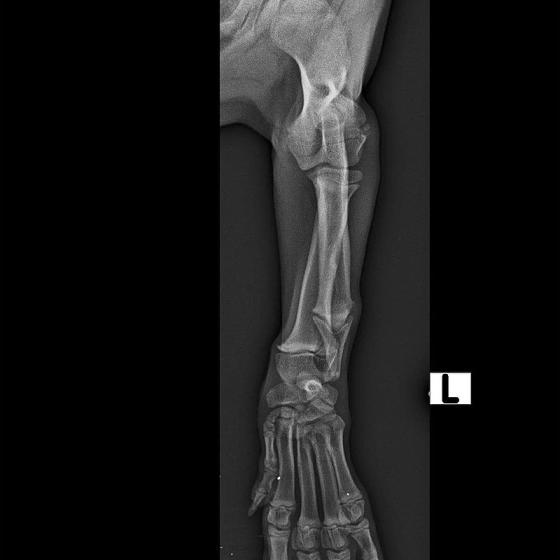

Odoberal sa od drogovo závislých asociálov, ktorý boli vysťahovaný z domu. Ihly, striekačky, ľudské výkaly, rôzne neidentifikovateľné zvratky, špinavé oblečenie, použité kondómy - to všetko nahádzané na jednu kopu v obývačke, kde Pluto so svojou maminkou Miou žili. :( Nevieme ako sa to stalo, kto mu ublížil, ale Pluto má prestrelenú prednú nohu! Viete si predstaviť toho psychicky narušeného človeka, ktorý strieľa na malé bezbranné šteniatko? V dôsledku strelnej rany má doslova rozdrvenú lakťovú kosť. Mali sme veľké obavy, že o nožičku príde, ale MVDr. Vatolík s teamom veterinárnej kliniky Sibra centrum opäť urobil zázrak a malému nožičku napravil a prognóza je viac než dobrá. Čaká ho ešte dlhá cesta k zotaveniu, ale je to odvážny a statočný bojovník. Nechceme si ani len predstaviť čím všetkým si tie zvieratká muesli prejsť, a kto vie koľko ich pôvodne bolo.. Nikto nevie ako a kde skončili Plutovi súrodenci...